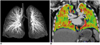

CT techniques are continuously evolving. For cardiac applications, second-generation dual-source CT and large-coverage volume CT (256-320 slices) have come into the spotlight (14, 23). On top of the higher spatial resolution and longer coverage, other innovative technical developments are waiting for the initial clinical results. They include 1) a high-pitch (up to 3.4) dual-source spiral scan, 2) a dual-energy lung perfusion and ventilation scan (Fig. 14), 3) a new type of tube current modulation to reduce the radiation dose to superficial radiation-sensitive tissue such as the breast, the thyroid gland or the eyeball, 4) automatic suggestions for the CT dose parameters according to the individual clinical task and the anatomic region, and (5) combined triggering of the ECG and respiration (Fig. 8).